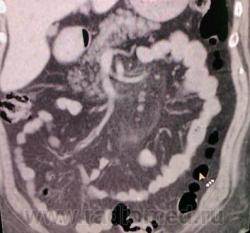

Прошу помочь КТ-специалистов. Медсестра 68 лет, частые боли в позвоночнике, непостоянные боли в животе. Направлена неврологом для исключения грыжи МПД поясничного отдела. Выявлены дегенеративные вараженные изменения позвоночника. По УЗИ норма, Hb=116 (начало 2009).На КТ: в брыжейке тощей кишки уплотнение жировой клетчатки (-45...-60ед.Н) размерами 12х5х7 см, окружает верхнебрыжеечную артерию, пронизано сосудами. Лимфоузлы брыжейки 0.5-1-1.5 см. Парааортальные л/у единичные, не увеличены.Контрастирования не проводилось - амбулаторное обращение. В понедельник давать заключение. Подозреваю ангиолипому. Буду рекомендовать обследование в стационаре.

Реконструкции

В вашем случае виден очень характерный для панникулита симптом ободка нормальной жировой плотности вокруг сосудов (симптом halo), ход сосудов не изменен, смещения или сдавления нет.